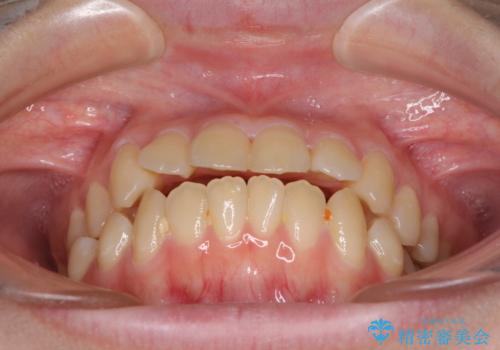

上下の出っ歯を治したい ワイヤー装置による抜歯矯正

口元の突出感は著しく改善され、横顔の印象が大きく変化しました。